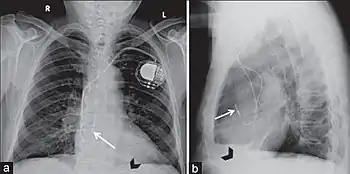

أجهزة تنظيم و تقويم ضربات القلب

مقالات مفصلة: مقوم نظم القلب مزيل الرجفان القابل للزرع- ناظمة قلبية اصطناعية

يتم وضع أجهزة تنظيم ضربات القلب الداخلية و الناظمات القلبية من خلال القسطرة أيضًا. الاستثناء من ذلك هو وضع أقطاب كهربائية على السطح الخارجي للقلب (تسمى الأقطاب الكهربائية النخابية). خلاف ذلك، يتم وضع الأقطاب الكهربائية من خلال الجهاز الوريدي إلى القلب وتترك هناك بشكل دائم. عادةً ما يتم وضع هذه الأجهزة في الجزء العلوي الأيسر من الصدر وتدخل الوريد تحت الترقوة الأيسر ويتم وضع الأقطاب الكهربائية في الأذين الأيمن والبطين الأيمن والجيوب التاجية (لتحفيز البطين الأيسر).